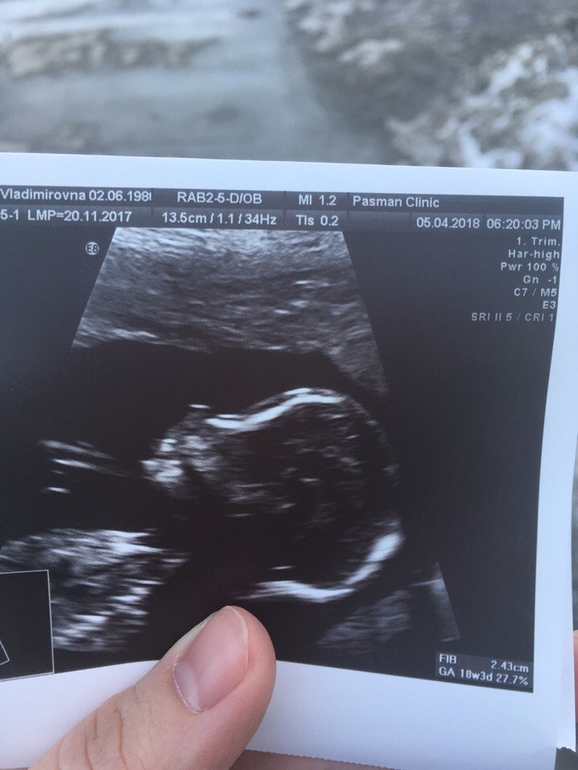

Сегодня были на втором скрининге.Срок 19 недель и 3 дня.Правда малышу поставили ровно 19 недель.Но врач сказал,что на это даже не стит обращать.

В остальном все идеально.Вес 300 грамм,ростик 14 см.